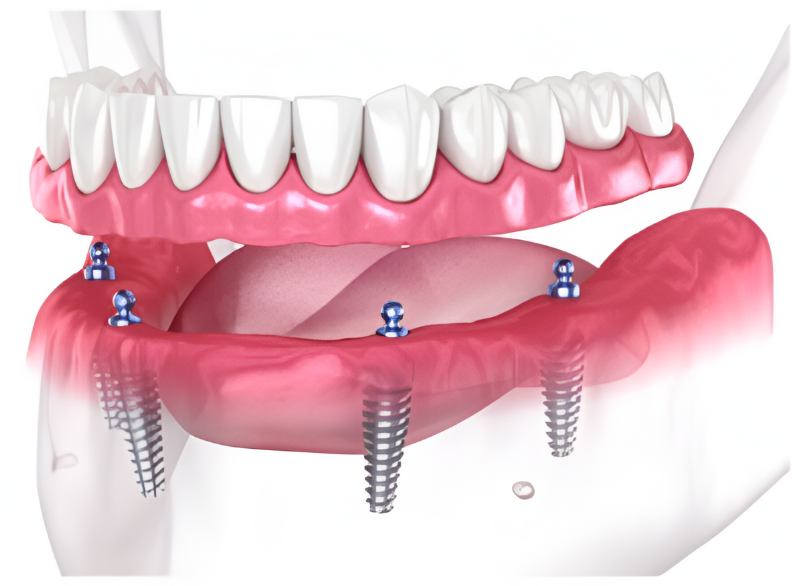

So, how do they work?

Every single dental implant consists of three parts - the implant, the abutment, & the crown. The implant is made of medical grade titanium. This part is surgically placed into the patient’s jaw bone and left to heal for 4-6 months afterwards.

This implant piece acts as the foundation for the rest of the tooth. Once the bone around the site has healed, the abutment and crown are placed on top of the implant. The end result is a beautiful, natural-looking new tooth!

Few people will ever be able to tell the difference between your implants and your real teeth.